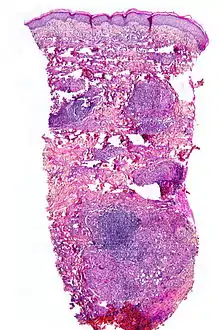

Micrograph showing necrobiosis lipoidica in a punch biopsy.

NL is diagnosed by a skin biopsy, demonstrating superficial and deep perivascular and interstitial mixed inflammatory cell infiltrate (including lymphocytes, plasma cells, mononucleated and multinucleated histiocytes, and eosinophils) in the dermis and subcutis, as well as necrotising vasculitis with adjacent necrobiosis and necrosis of adnexal structures. Areas of necrobiosis are often more extensive and less well defined than in granuloma annulare. Presence of lipid in necrobiotic areas may be demonstrated by Sudan stains. Cholesterol clefts, fibrin, and mucin may also be present in areas of necrobiosis. Depending on the severity of the necrobiosis, certain cell types may be more predominant. When a lesion is in its early stages, neutrophils may be present, whereas in later stages of development lymphocytes and histiocytes may be more predominant.